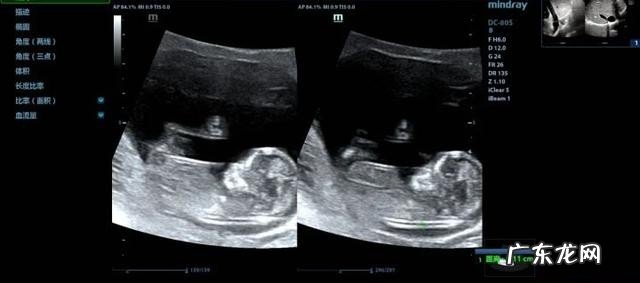

文章插图

正常NT的厚度随孕龄增长而增厚,至孕13周达最大,中孕期自发消退 。最佳测量时间为孕11-13+6周 。NT厚度测量的正常值<3mm 。